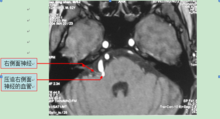

核磁顯示右側面神經在出腦幹處被一血管壓迫